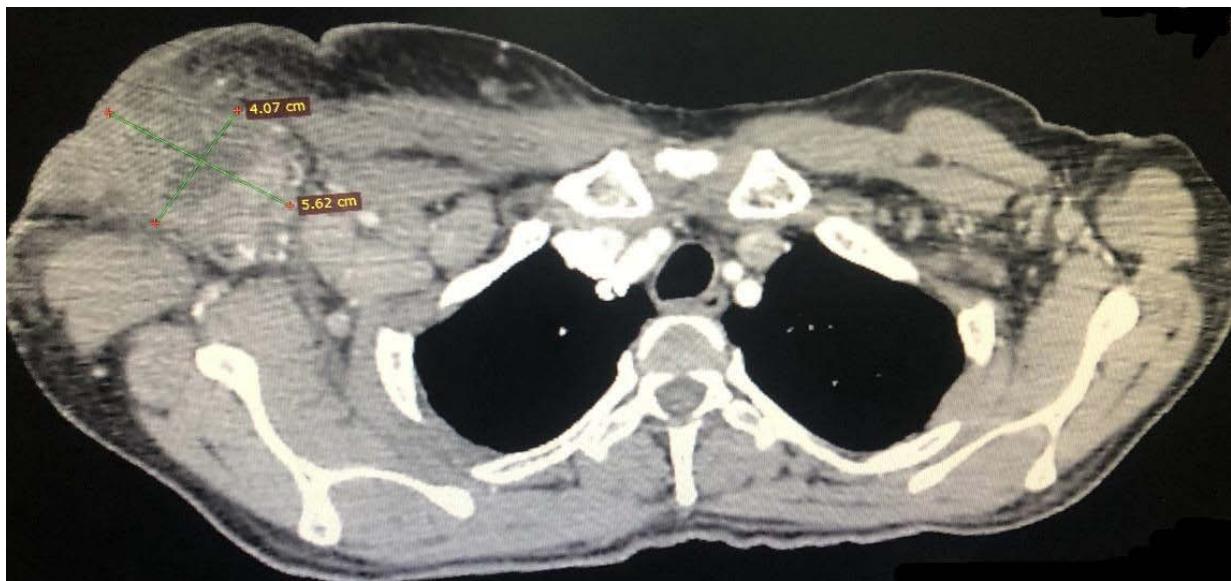

Computed tomography of the chest showed the presence of confluent lymphadenomegaly in the right axillary chain, forming a mass with a center of necrotic, measuring approximately $56 \times 40 \mathrm{~mm}$ in their largest diameters. Other non-confluent lymph nodes of increased size were observed in the ipsilateral axillary chain, left axillary chain and retroperitoneum. Abdominal CT scans showed prominent lymph nodes in the common iliac chain and bilateral inguinal nodes.

C Fig. 3: (A) CT scan of the right axillary region showing confluent lymph nodes forming a mass with a necrotic center measuring approximately $56 \times 40 \mathrm{~mm}$ in its largest diameters; (B and C) CT scan showing lymphadenopathy in chains in the right inguinal region and the right common iliac region respectively.